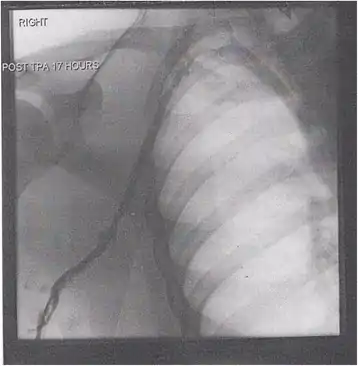

A venogram before catheter-directed thrombolysis for Paget–Schroetter syndrome, a rare and severe arm DVT shown here in a judo practitioner, with highly restricted blood flow shown in the vein

After treatment with catheter-directed thrombolysis, blood flow in the axillary and subclavian vein were significantly improved. Afterwards, a first rib resection allowed decompression. This reduces the risk of recurrent DVT and other sequelae from thoracic outlet compression.[147]